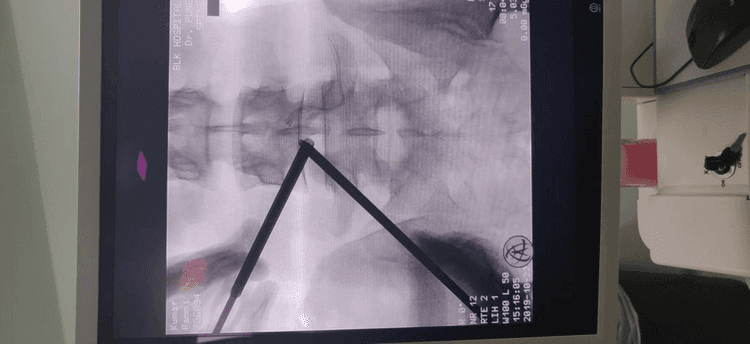

Unilateral biportal endoscopic (UBE) decompression technique is a percutaneous, full-endoscopic approach. Performed through two small incisions on either side of the spinous process, UBE allows freedom from the restrictions of working tubes or channels. With continuous high-pressure saline irrigation and a high-definition arthroscope, the surgeon can achieve precise decompression with a clear and magnified surgical field.

UBE endoscopy is an excellent alternative to microscopic-assisted minimally invasive surgery. Developed to improve muscle preservation and maintain surrounding normal anatomical structures, UBE has significant benefits over open spinal surgery.